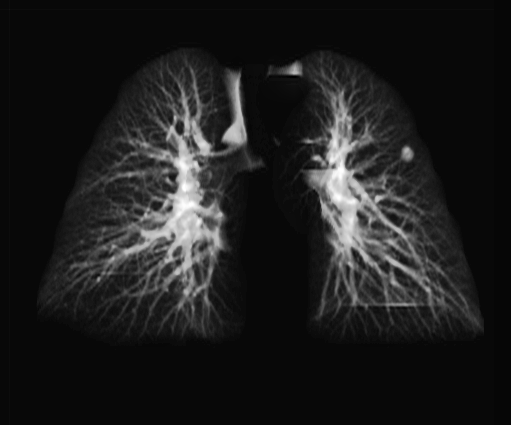

3.3 Applicability to Real X-ray

In order to explore the applicability of our algorithm to real X-ray and to examine whether the enhancement scheme introduces artifacts detrimental to CAD detection performance, we chose to perform the lung enhancement algorithm as a preprocessing step on nodule and mass CAD input images.

To accomplish this, we trained and tested a CheXNet [5] based network on 67,313 images released in ChestX-ray14 dataset(subset of PA images). In Figure 8 we show the results of the enhancement on an image from NIH ChestX-ray14 dataset [4]. The architecture we chose was a DenseNet-121 based network, with 512×512512512512\times 512 input size. Network weights were initialized with pretrained ImageNet weights and training was performed independently for enhanced images and non-enhanced images.

The dataset was split to 44,971 training, 11,245 validation and 11,097 test images. Results are given on the official test set in terms of average precision (AP) for the labels mass and nodule. We see a moderate increase in AP scores for the mass detection task (Table 2).

Refer to caption

(a)

(b)

(c)

(d)

Figure 8: Enhancement result on NIH ChestX-Ray14 image. One network was trained on the original X-ray and a second network was trained on the enhanced X-ray (a) Original X-ray (b) Enhanced X-ray (c) Zoom (d) Zoom -Enhanced